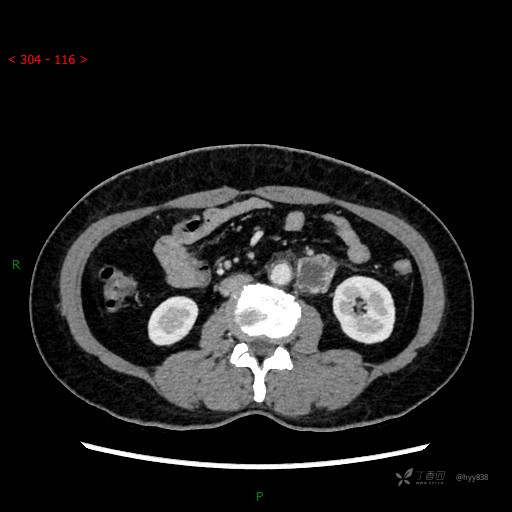

增强动脉期

CT平扫是外院的,因图像质量原因,不方便上传!